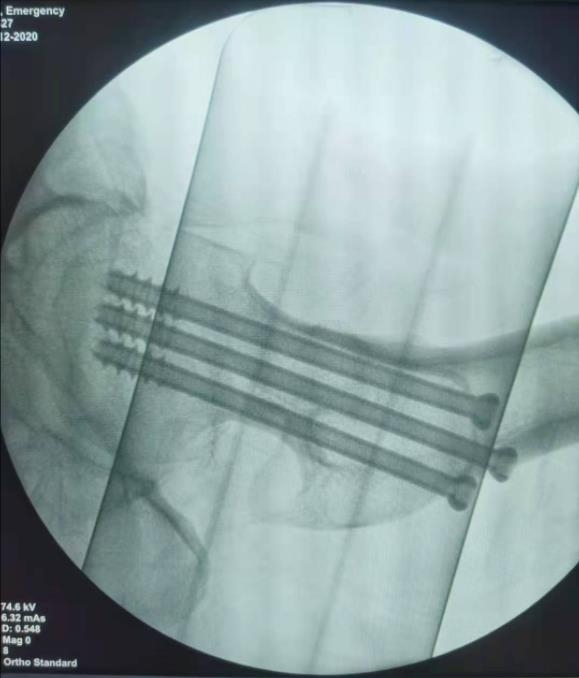

闭合复位经皮固定手术步骤

1、经皮沿股骨颈轴线置入空心钉导针,确保导针平行;

2、标准放置螺钉为倒三角形,其中下方螺钉在股骨矩,后方螺钉在后方骨皮质、研究发现倒三角形平行三枚螺钉能提供最佳的固定强度;

3、螺钉位于股骨颈四周,特别是后侧及下方,避免低于小转子方向进针,可能导致术后转子下骨折;

4、两个平面透视导针位置良好后切开皮肤,空心钻铭孔,导针引导下拧入空心钉,空心钉确保所有螺纹位于骨折线近端,螺钉头应距离软骨下骨5mm。

空心钉固定的三原则:“贴边、平行、倒品”

1、贴边是指3枚螺钉在股骨颈内,尽量靠近外围皮质。这样3枚螺钉作为一个整体,对整个骨折面可形成面状加压,如果3枚螺钉不够离散,更趋于点状加压,稳定性较差,不能较好地对抗扭转和剪切。

有研究显示,在侧位片上,螺钉的前后分布越分散,骨折不愈合发生率越低。J Bone Joint Surg Br. 2005 May: 87(5): 632-4.

图1 3枚螺钉在股骨颈内的理想位置

2、倒品有更明显的生物力学优势,CORR曾发表美国学者的一项生物力学研究,对比两种固定方式出现再骨折的负荷大小,发现倒三角再骨折的平均负荷11330N,而正三角仅7795N,差异明显,也就是说倒三角形固定可使再骨折的负荷提升45%。

图2 倒品字固定

3、平行生物力学更稳定。